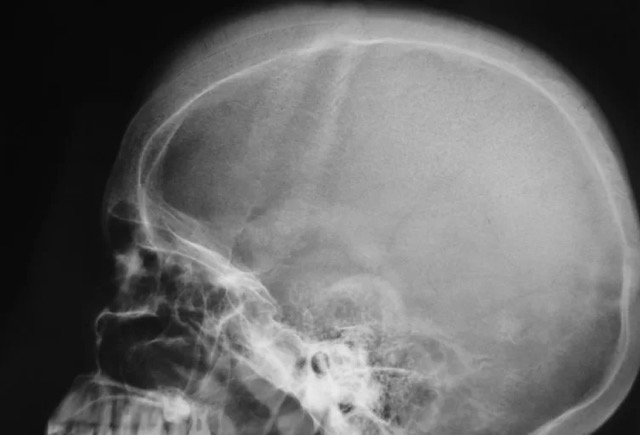

O neuroblastoma é o terceiro tipo de câncer mais recorrente entre crianças, depois da leucemia e de tumores cerebrais. É o tumor sólido extracraniano mais comum entre a população pediátrica, representando 8% a 10% de todos os tumores infantis.

Foto: Reprodução